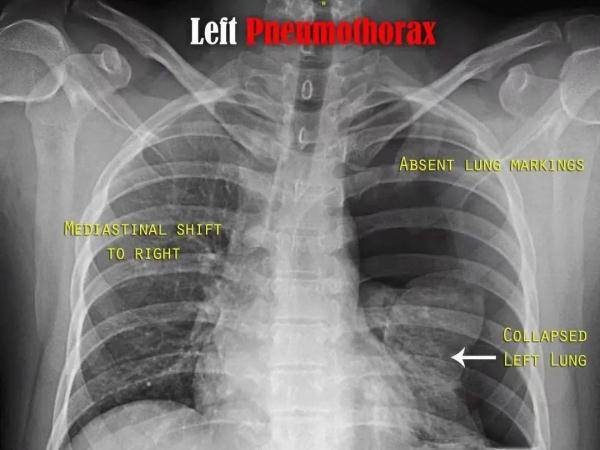

“俗话说的肺‘炸’了 , 其实就是医学上的自发性气胸 , 一般是因为非外力因素导致肺大泡破裂 , 使得肺里面的气体进入胸膜腔 , 出现胸闷、呼吸困难等不适症状 。 ”温医大附二院重症医学科副主任医师张晓隆介绍说 , 胸腔就像个封闭的盒子 , 而胸腔中左右两肺就像盒子中的两个气球 。 气胸就是肺像气球一样破了 , 胸腔内就会充气 , 严重时气胸会使人难以呼吸 , 甚至压迫大血管 , 或使心脏及血管移位 , 导致循环衰竭 , 有致命的风险 。

“有可能是因为胸腔压力的突然增加而破裂 , 从而发生自发性气胸 。 换句话说 , 大部分自发性气胸的患者曾在发病前有打篮球、跑步等运动的情况 , 甚至一些人睡觉翻个身也会发生气胸 。 ”张晓隆介绍说 , 这类疾病通常发生在瘦高型人群中 , 这是因为瘦高体型的患者胸廓比较大 , 肺部为了适应胸廓的容量也会随之增大 , 肺弹力纤维发育不良导致肺泡弹性减退 , 扩张后引起肺大泡 。